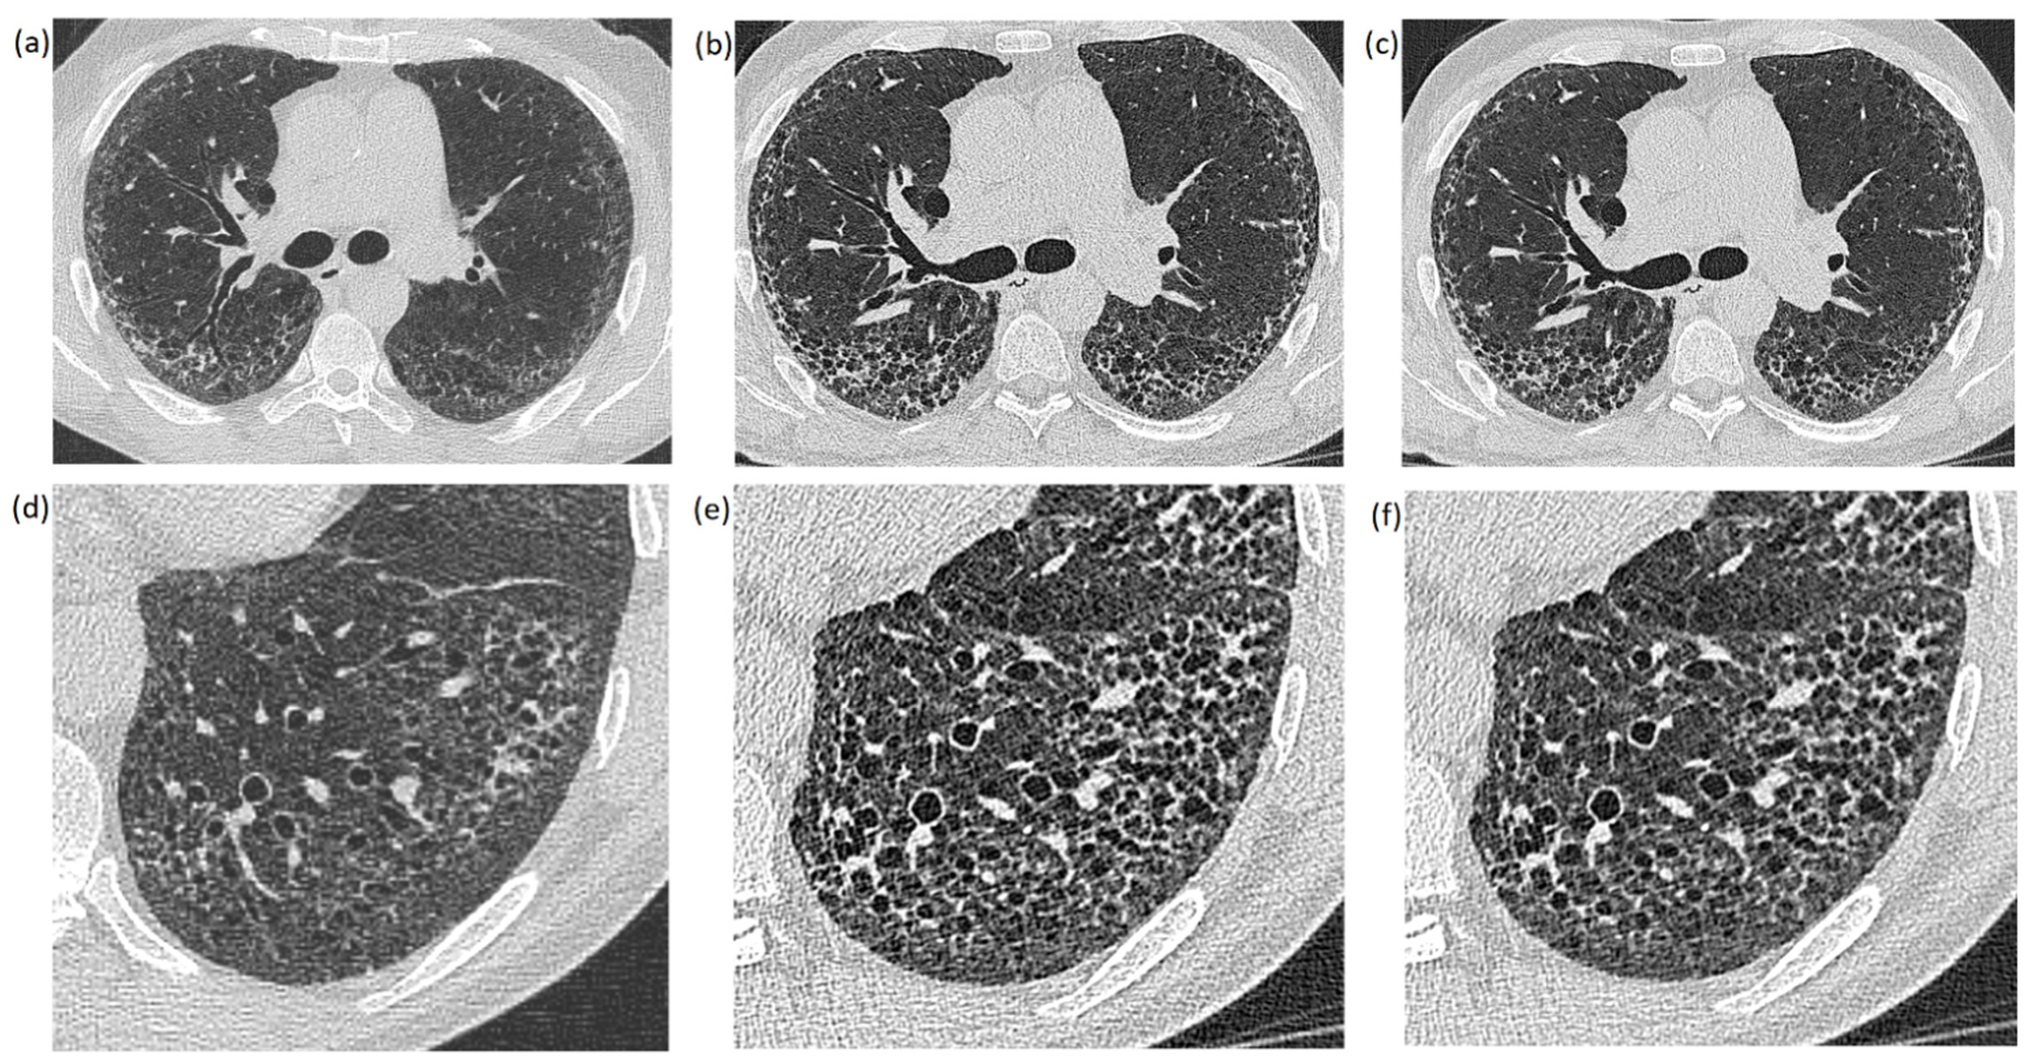

Low-Dose High-Resolution Photon-Counting CT of the Lung: Radiation Dose and Image Quality in the Clinical Routine

- Sartoretti, T.; Racine, D.; Mergen, V.; Jungblut, L.; Monnin, P.; Flohr, T.G.; Martini, K.; Frauenfelder, T.; Alkadhi, H.; Euler, A. Quantum iterative reconstruction for low-dose ultra-high-resolution photon-counting detector CT of the lung. Diagnostics 2022, 12, 522. [Google Scholar] [CrossRef]

- Symons, R.; Pourmorteza, A.; Sandfort, V.; Ahlman, M.A.; Cropper, T.; Mallek, M.; Kappler, S.; Ulzheimer, S.; Mahesh, M.; Jones, E.C.; et al. Feasibility of dose-reduced chest CT with photon-counting detectors: Initial results in humans. Radiology 2017, 285, 980–989. [Google Scholar] [CrossRef]